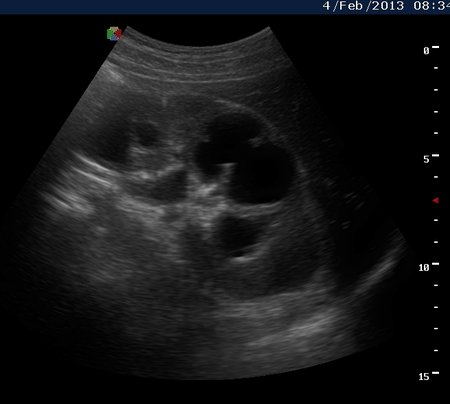

Вот как выглядит почка при первом осмотре и в феврале

1.jpg

3февраль.jpg

Почку не убрали, лечат. Диагноз поставили бактериоскопически.